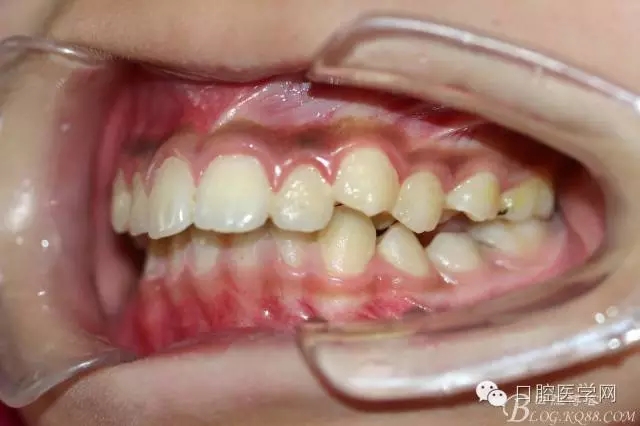

正畸查:替牙合。第一恒磨牙中性合。上牙弓尖圓型下牙弓方圓型。前牙覆合3度覆蓋7.5mm。下前牙咬到上舌側(cè)牙齦。上頜擁擠4.0mm,下頜擁擠

3.0mm。上頜稍前突下頜后縮,上下唇前突,上前牙覆蓋下唇,下唇外翻。面下三分之一過短,頦唇溝明顯,開唇露齒,頦饜窩明顯。顳下頜關(guān)節(jié)開閉口無彈響,無壓痛,開口型開口度正常。

正畸前照片: